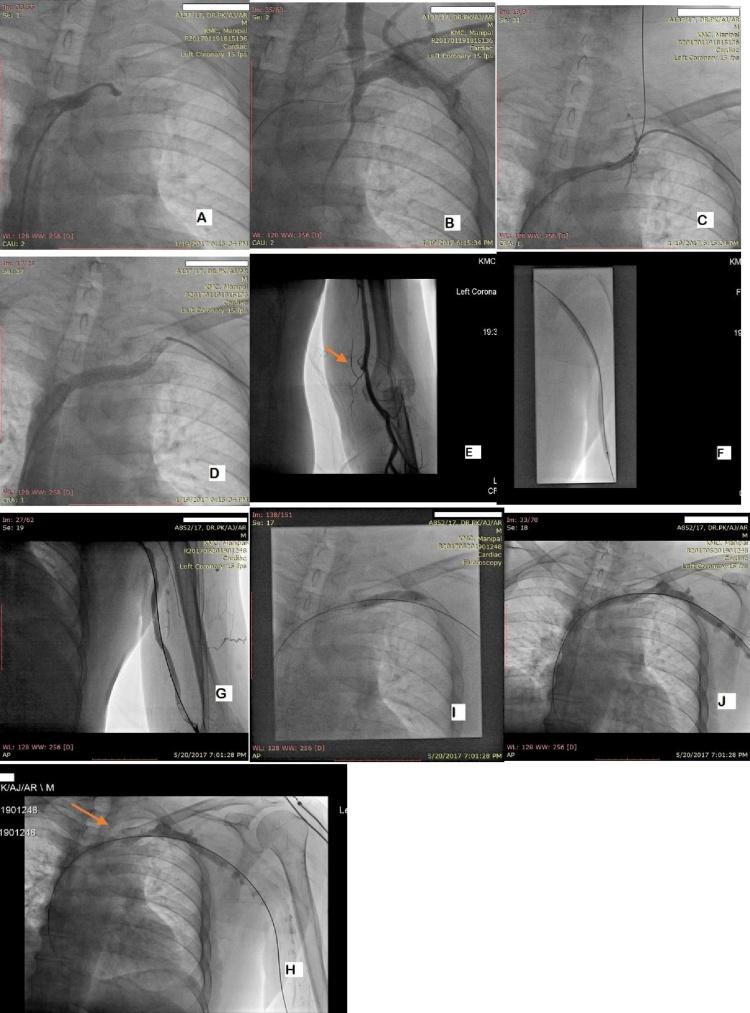

Percutaneous intervention for symptomatic central vein stenosis in patients with upper limb arteriovenous dialysis access.

The present study was done to determine feasibility and clinical success of endovascular approach for the treatment of symptomatic central venous stenosis associated with significant ipsilateral limb edema in dialysis patients with vascular access in the upper limb.

A database of hemodialysis patients who underwent endovascular treatment for central venous stenosis from January 2014 to January 2017 at our institute was retrospectively reviewed. Follow-up was variable.

The study included ten patients (6 men and 4 women) with a mean age of 45.2 years, who underwent thirteen interventions during a period of 3 years. The technical success rate for endovascular treatment was 100%. One patient underwent primary PTA (percutaneous transluminal angioplasty). Seven patients underwent primary PTA and stenting. Three patients underwent secondary PTA. One among these patients underwent secondary PTA twice along with fistuloplasty. One patient underwent secondary PTA with stenting. No immediate complications were encountered during the procedure. Our study shows a primary patency rate of 67% and 33% at 6 months and 12 months for PTA with stenting. Our study also shows secondary or assisted primary patency of 75% at 6 months of follow-up.

Endovascular therapy (PTA) with or without stenting for central venous stenosis is safe, with low rates of technical failure. Multiple additional interventions are the rule and long-term patency rate is not very good.